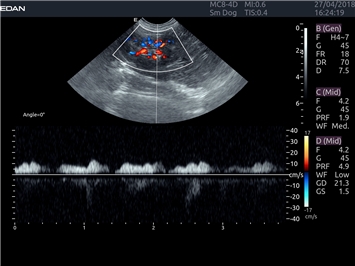

EDAN Acclarix LX4 VET представляет собой профессиональную ультразвуковую систему, специально разработанную для ветеринарных исследований. Сочетание стабильности, высокой производительности и эффективности делает эту систему идеальным выбором для современной ветеринарной практики.

Цветовой допплер:

Да

Импульсно-волновой допплер: